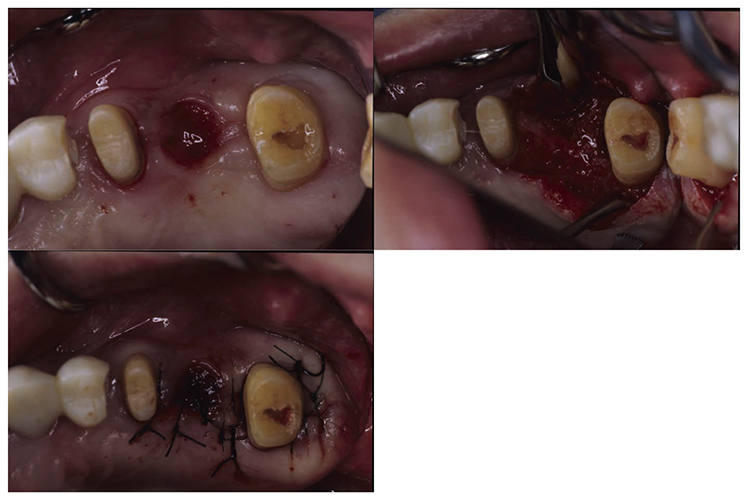

3) Periodontal surgical therapy

At the reevaluation examination after completion of basic periodontal treatment, deep periodontal pockets and grade 2 furcation involvement were observed. Therefore, in April 2010 (age 42), enamel matrix proteins were applied in a procedure for periodontal regeneration (Fig.4),and in June of the same year, gingival flap operation and distal wedge procedure were performed on 27 (Fig.5). For the remaining PD on the lingual side of 36 and 46, due to insufficient keratinized gingiva, the option was to stabilize the condition with SRP.

Fig 4

(Fig.4) Enamel matrix proteins were applied in a procedure for periodontal regeneration in the maxillary left molar (April 1, 2020)

Fig 5

(Fig.5) Gingival flap operation and distal wedge procedure were performed on the maxillary left second molar (June 2010)